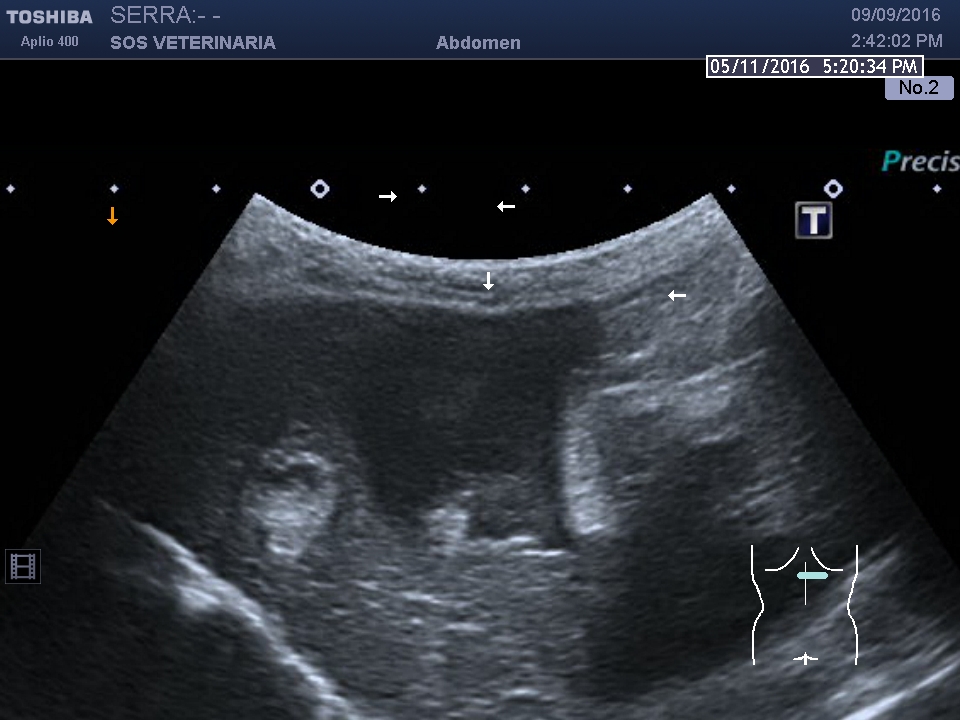

Gatta comune europea ,eta’ 5 anni ,improvvisa debolezza,vive in casa ,alla visita: mucose pallide,lieve distensione addome ,l’ecografia di base evidenzia emoperitoneo (versamento campionato) e due masse di alcuni centimetri ipoecogene peritoneali a profilo uniforme avascolari al color doppler , lesioni focali epatiche alcune molto demarcate ed ecogene altre consistenti in aree piu’ o meno demarcate con settori ane-ipoecogeni e settori ecogeni , demarcazione del profilo dei lobi nelle porzioni caudali meno definito.

Osservando il grado di compromissione epatica e le lesioni macroscopiche del soggetto colpisce come sempre per noi ecografisti la discrepanza tra imaging e realta’ ,la deformazione del profilo lobare e le lesioni nodulari esofitiche e disorganizzanti la superficie lobare dell’organo ,non erano poi cosi evidenti all’esame ultrasonografico